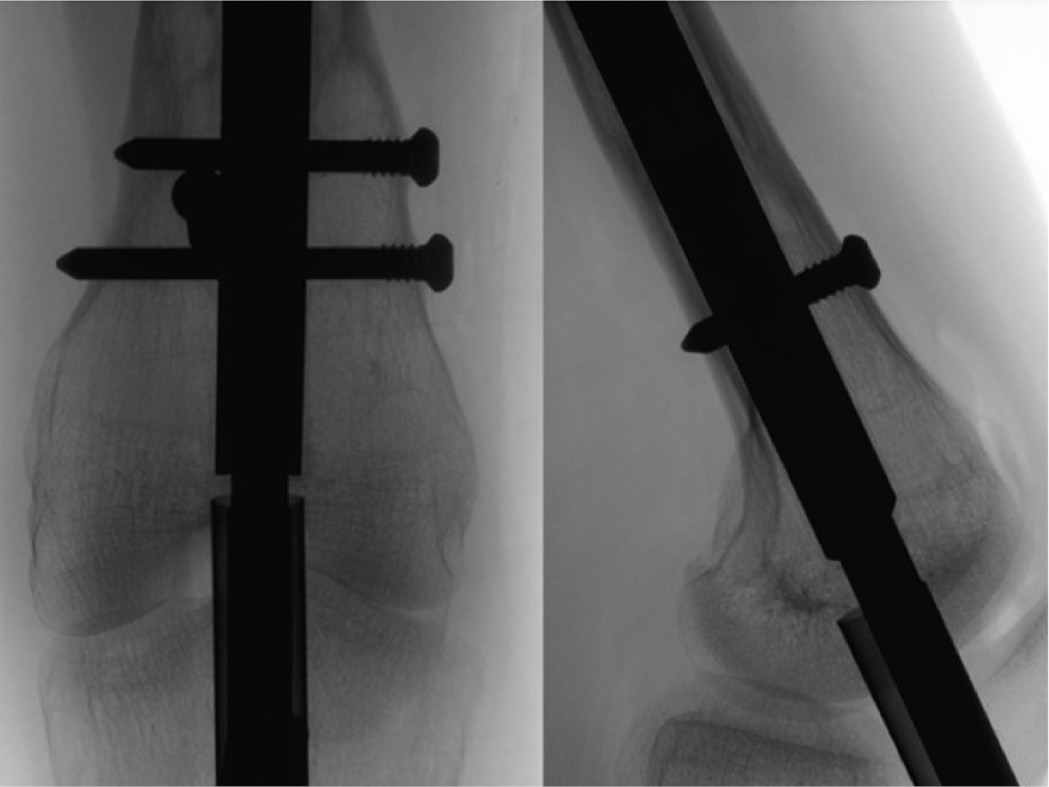

Figure 4. Rotate the limb until the distal interlocking elements are in perfect profile. This will help determine if there has been any bone growth over the top of the fixation elements that might preclude a percutaneous removal attempt. It is additionally advised to use this position to remove the screw. Placing the screwdriver in-line with the screw in perfect profile and perpendicular to the fluoroscopy beam will ensure proper orientation and facilitate engagement into the screw head.

jposna20220031_fig4.jpg